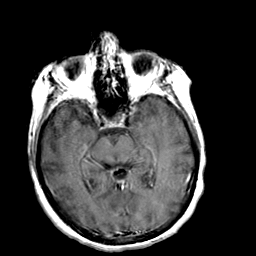

Creutzfeld-Jakob disease: gadolinium enchanced T1-Weighted MR -- Slice #10

[Home][Help][Clinical] Slice 10